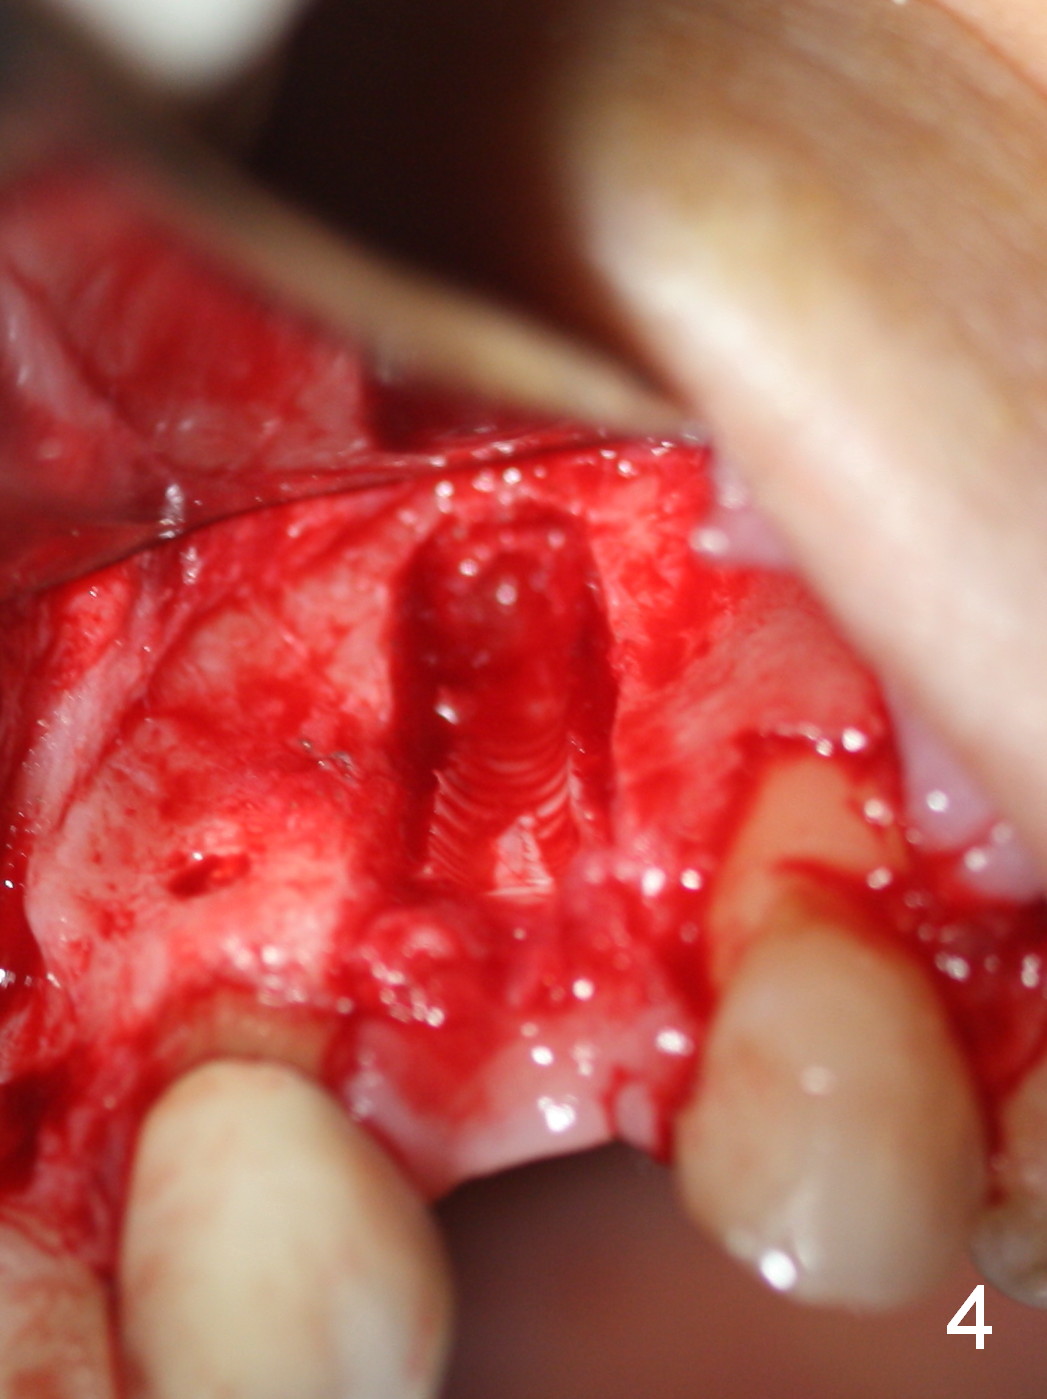

The 57-year-old lady does not like the crown at the site of #10 immediately when it is cemented (Fig.1). When the upper lip is retracted, it appears that the implant is immediately underneath the gingiva (Fig.2 *). It is slightly tender when palpated. The patient refuses CBCT. When the buccal flap is raised, the implant is found to be exposed buccally (Fig.3). When it is removed, the coronal portion of the palatal wall is thin (Fig.4). It appears that there is bone in the mid and apical thirds of the palatal wall, where an osteotomy is initiated using a 1.2 mm pilot drill. When the latter reaches 18 mm from the crest, the nasal floor appears to be perforated. The latter is confirmed by PA (Fig.5). As the osteotomy are increasing in diameter, force is applied as palatally as possible without perforating the palatal wall too much. When a 3.5x20 mm implant is placed (30 Ncm), it is palatal to the labial wall. The defect is filled by allograft and Osteogen, covered by long termed resorption membrane. The buccal flap is sutured (Fig.7). A proposal to place gingival graft is rejected. The implant is shown to have been positioned more or less normally (Fig.8). A removable temporary appliance is fabricated. Periodontal dressing is applied.